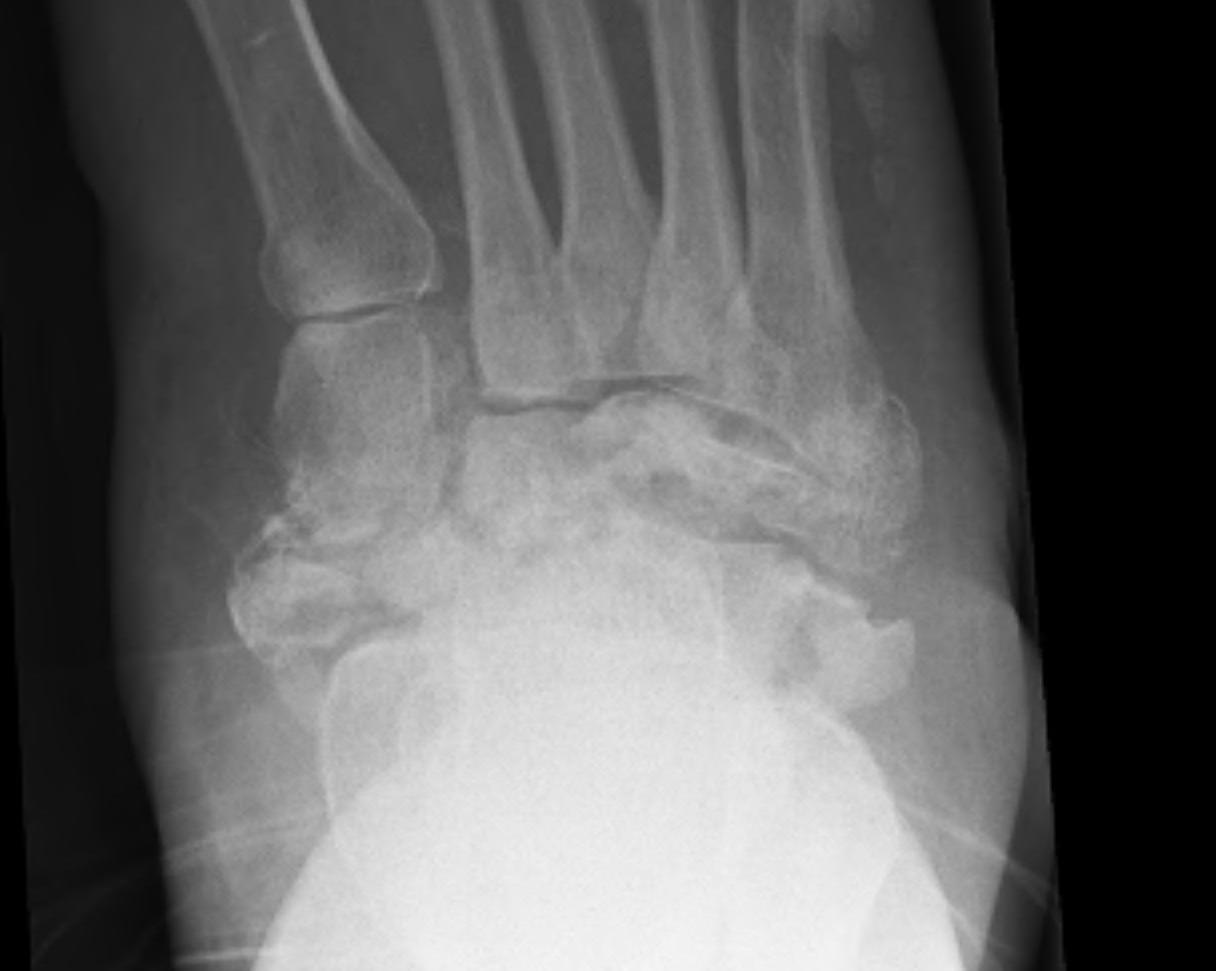

Demineralisation of regional bone Periarticular fragmentation Joint dislocation |

Midfoot dissolution, coalescence and reconstruction

Midfoot collapse

Midfoot collapse with subluxation of midtarsal joints